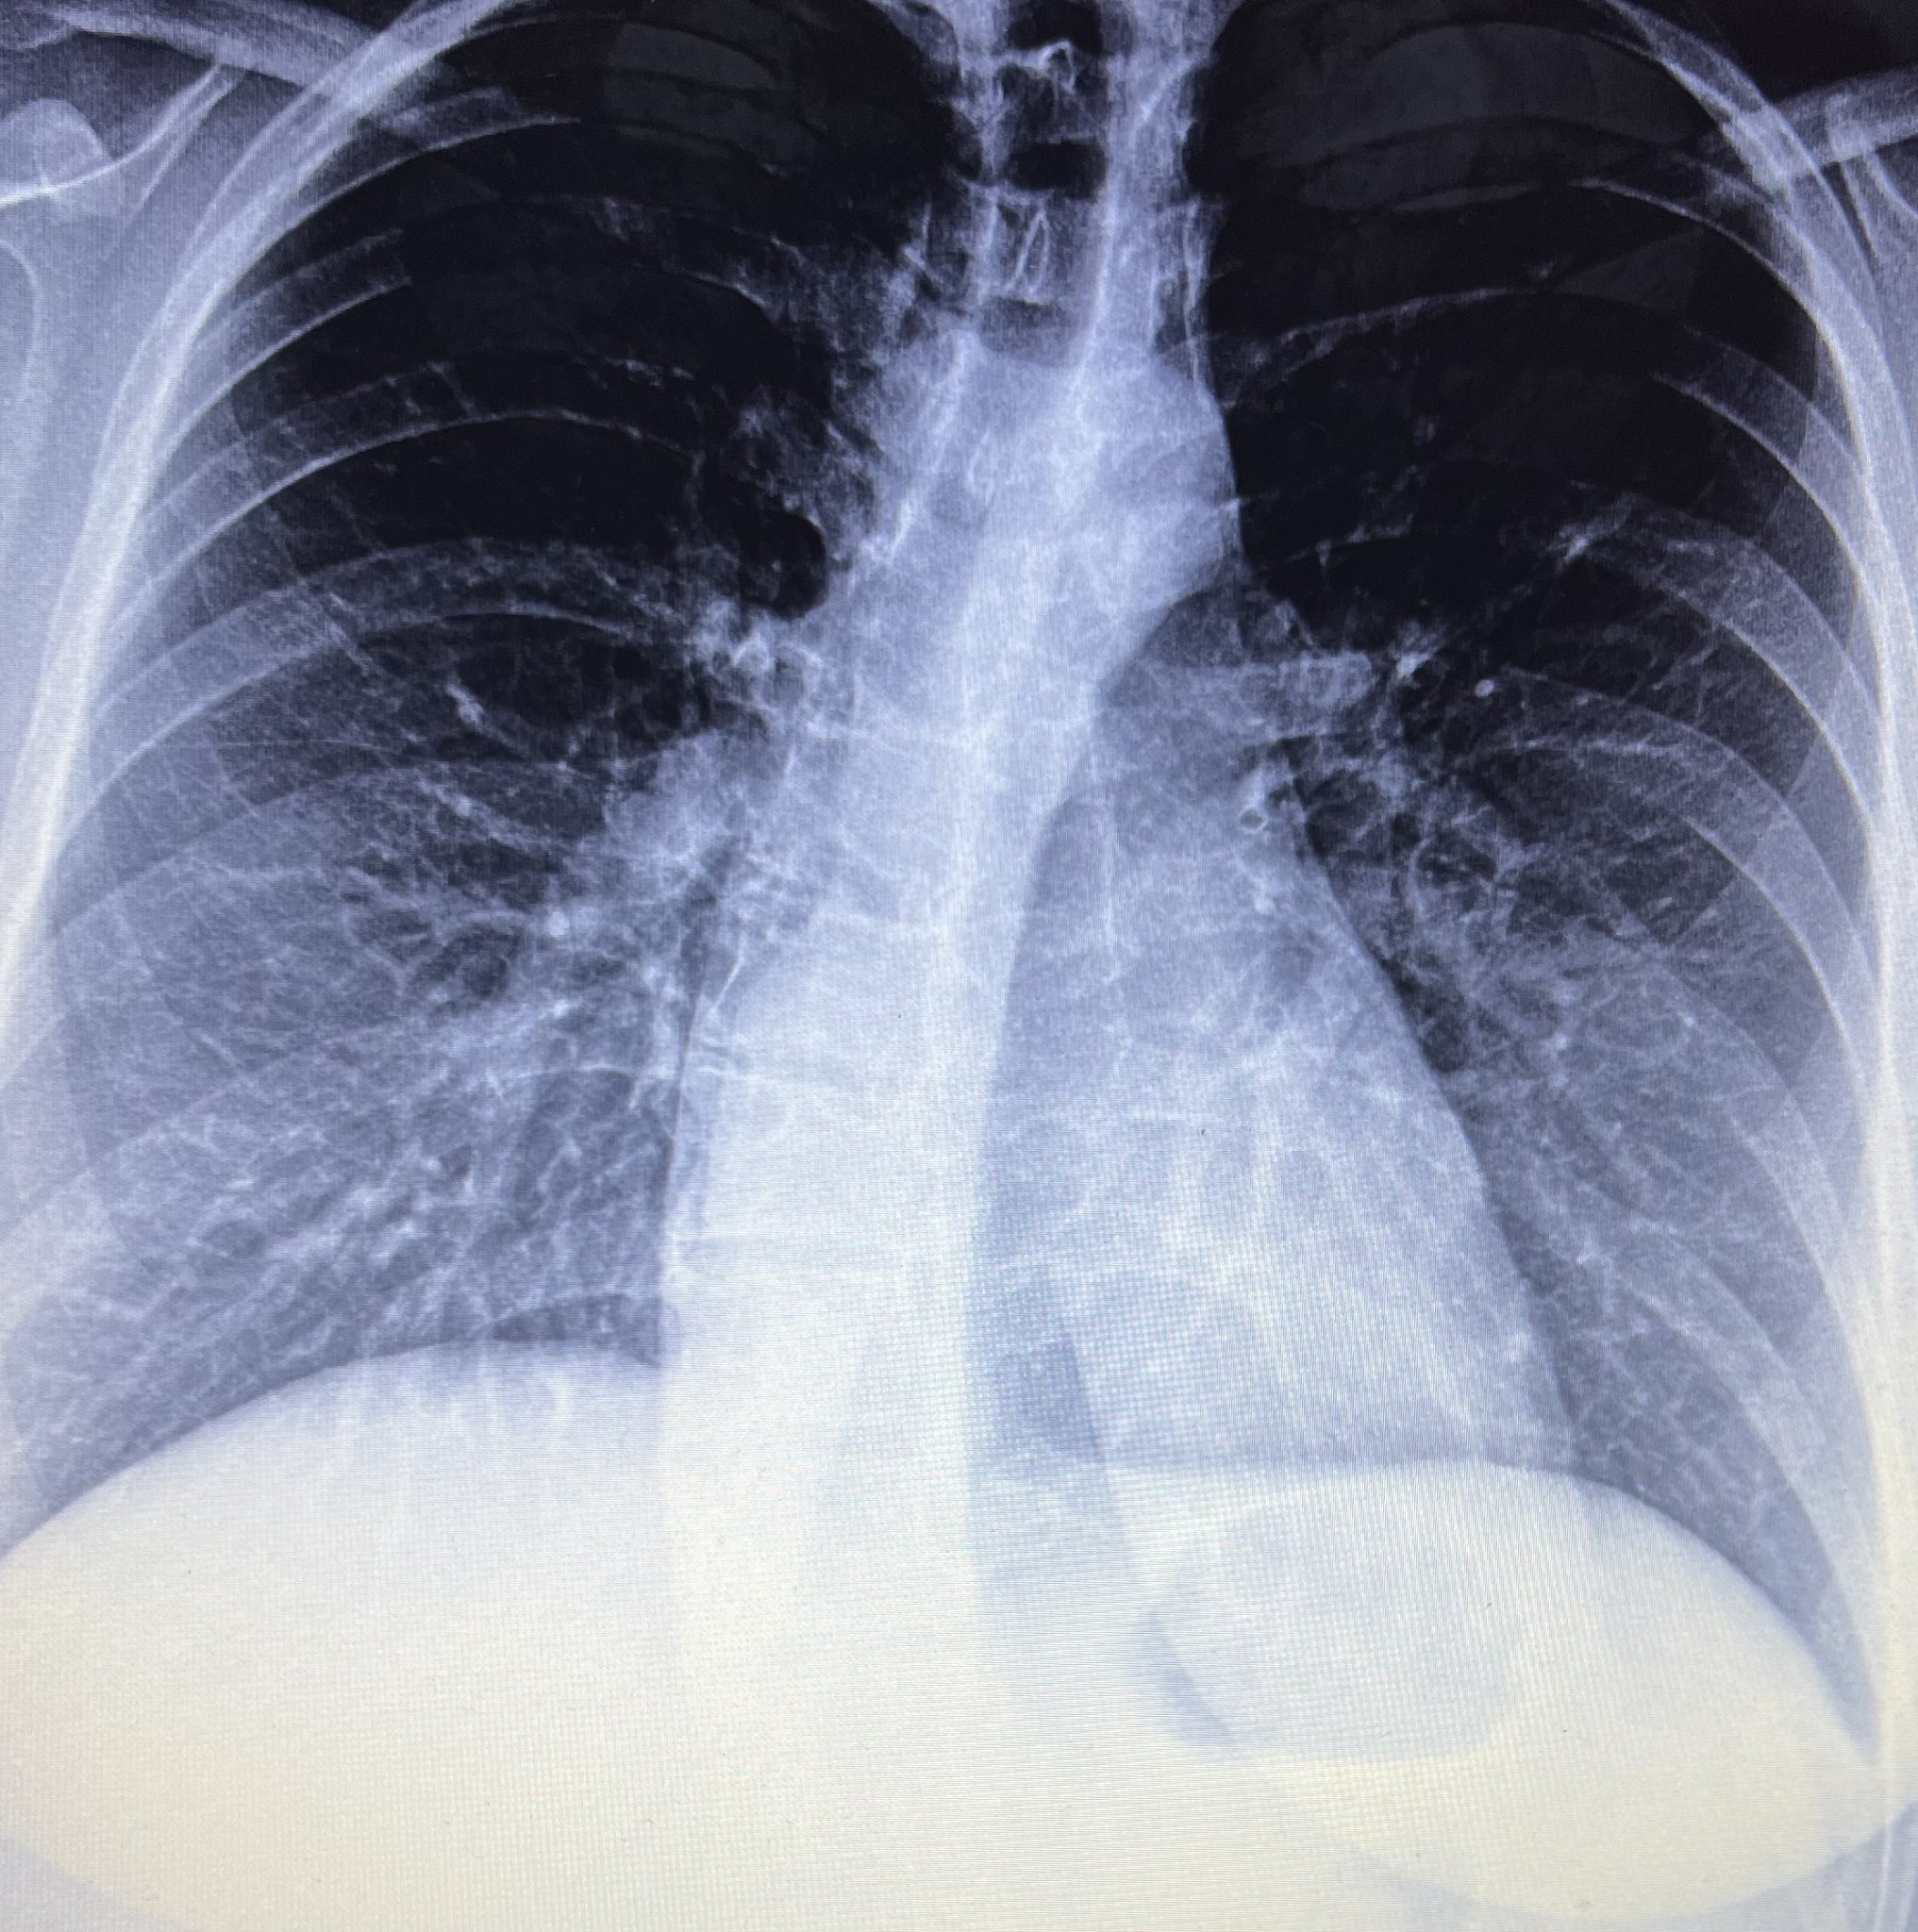

От 3 месеца съм с кашлица. Излезе ми снимката на белия дроб днес но лекарката е на смяна чак в Понеделник. Моля ако някой има идея да даде мнение. Рентгенолога е написал слабо усилен белодробен рисунък базално.всички изследвания са ми ок. Само леко завишени моноцити имам.

Освен възпаление на белия дроб имате и много тежко изкривяване на гръбначния стълб. Много изразено. Вземете някакви мерки, ще ви прави много проблеми във времето.

Да така е. Просто се чудех да белия дроб да не е нещо по-сериозно предвид тази продължителна кашлица и перфектни изследвания….

Или недолекувано или обострено хронично възпаление. Трябва да се лекува, за да се изчисти напълно.